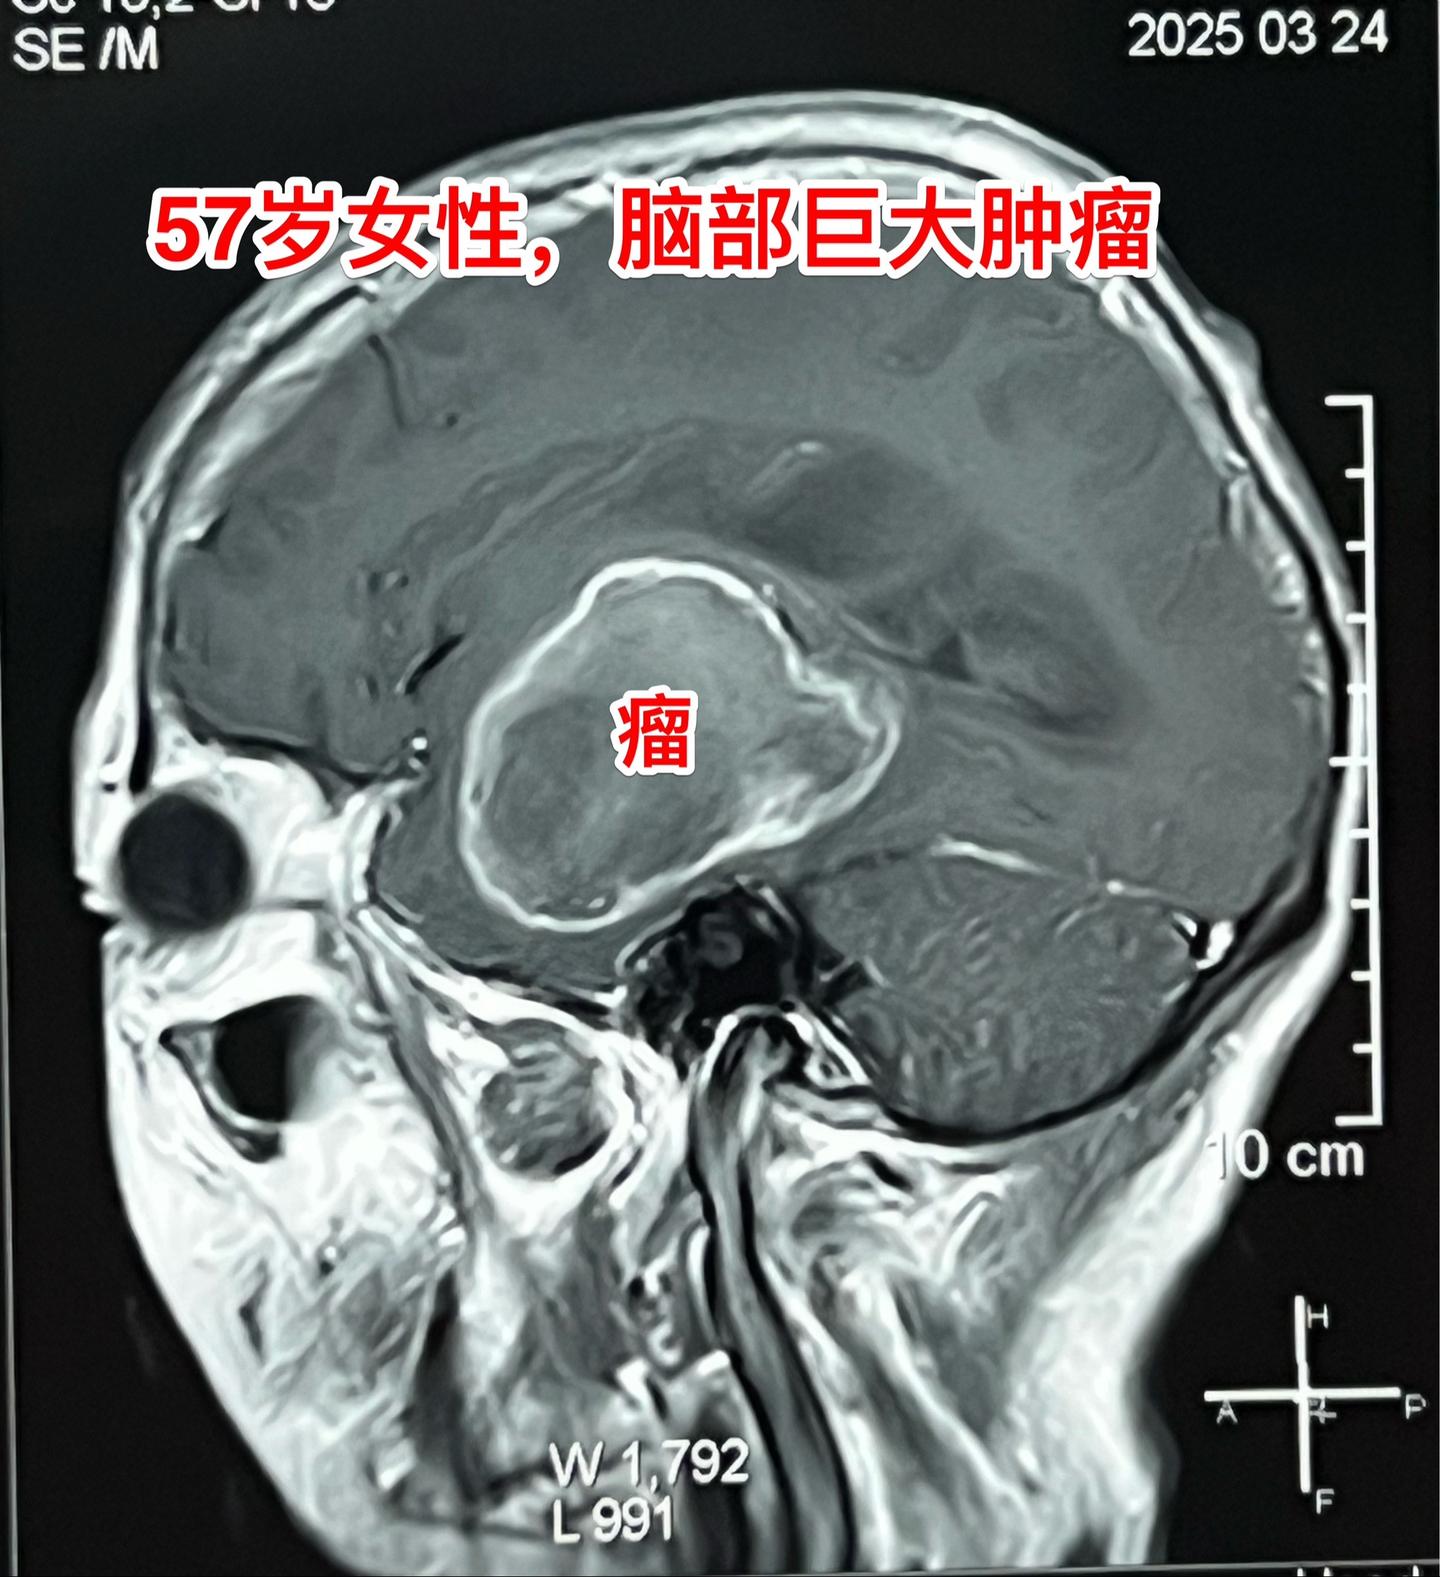

肺癌患者多年后出现脑部转移。57岁的韶关女病人在18年前患肺癌,作了手术切除肺癌并作了化疗,随后多次复查,没有发现肿瘤复发。她也在正常上班。 就在这个春节前她的婆婆去世了,她的情绪似乎受到严重影响,和平时不一样,总是担惊受怕。 三月份经家人提醒,到当地医院去作头部CT检查,结果发现脑部有个瘤,像鸡蛋那么大了!医生怀疑是胶质瘤。 3月22日到北京来找我住院。3月27日晚作了手术,手术中看见肿瘤形态符合肺癌脑转移。等待病理报告。